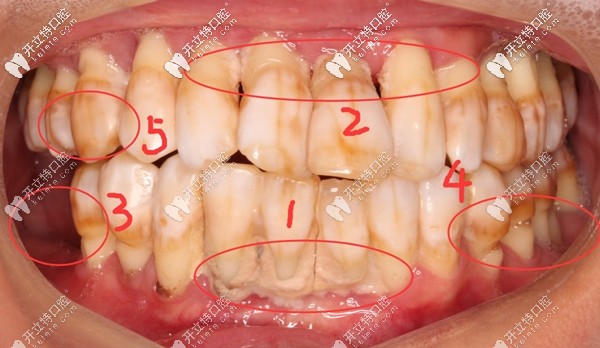

其實(shí)鄧?yán)蠋煹臐M口牙齒基本都在,但,一顆都留不住,因?yàn)槿慷紦u搖欲墜,牙根只有很淺一截在牙槽骨內(nèi),失去了咀嚼功能。

牙齒問題:①牙結(jié)石沉積 ;②重度牙周炎引起牙齦萎縮,牙根暴露;③牙齒楔形缺損;④四環(huán)素牙;⑤牙齒晚上痛到影響睡覺,痛的程度感覺已經(jīng)無法忍受了;⑥輕輕咬一點(diǎn)東西牙齒都在里面動(dòng)....